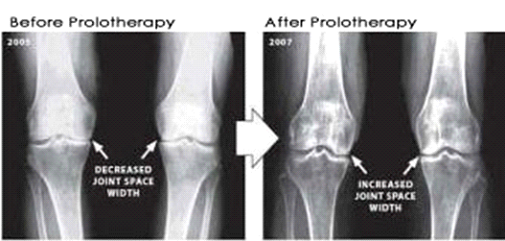

Joint and back pain can cause serious disruptions in people’s lives—from missing work to reduced mobility. Prolotherapy uses the body’s natural healing ability to alleviate chronic pain, strengthen damaged tissues, and restore function. It is a procedure in which a naturally occurring irritant is injected into the soft tissues of a damaged joint or area. This deliberate inflammation is designed to signal the body that there is a problem, so that our own bodies can cope by building new tissue. This can provide significant relief for joint or back pain.

Once activated, the body’s defenses and healing powers will begin to strengthen and repair damaged tissues. When it comes to joints, strengthening the connections in the area helps stabilize the joint and relieve pain over time.

Prolotherapy is also applicable in the area of the knee, hip and shoulder joints and connecting tissues. Indications that this kind of therapy is needed may include: sciatica, back pain, torn meniscus, distended tendons and ligaments, neck pain, rotator cuff disorders, tennis elbow, chest pain, leg pain and more. In some cases, people with chronic illnesses, such as degenerative disc disease or arthritis, may use prolotherapy to relieve the pain.